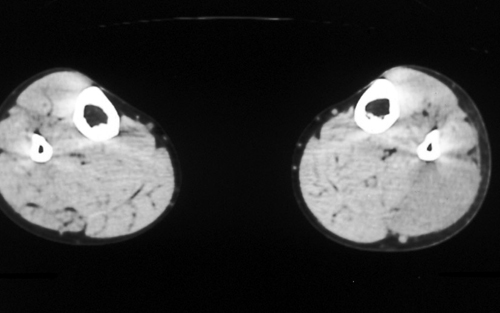

症例2:74歳、男性

下腿部腫瘤

6ヵ月前に左ふくらはぎに鈍痛があり、腫瘤に気づく。腫瘤は徐々に増大している。

図1 下腿部造影CT